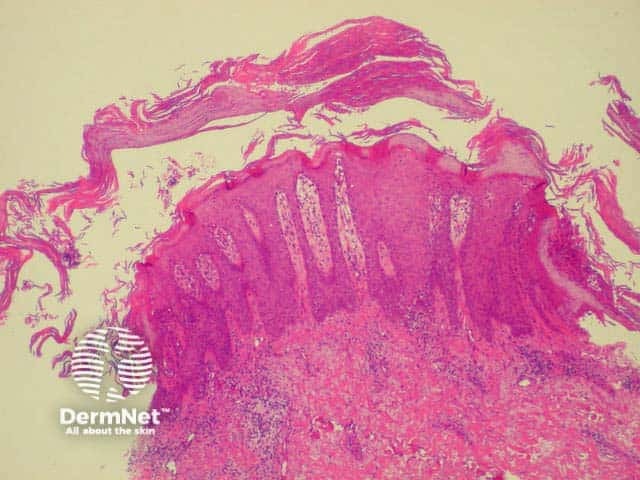

Histology of psoriasis is characterised by parakeratosis (cell nuclei within stratum corneum) and thickened projections of the prickle cell layer of keratinocytes (psoriasiform hyperplasia). There is no granular layer. Polymorphonuclear leukocytes and lymphocytes infiltrate dermis (CD8+) and epidermis (CD4+).

Thick stratum corneum and projections of epidermis Note inflammatory infiltrate Parakeratosis (cell nuclei within thickened stratum corneum)